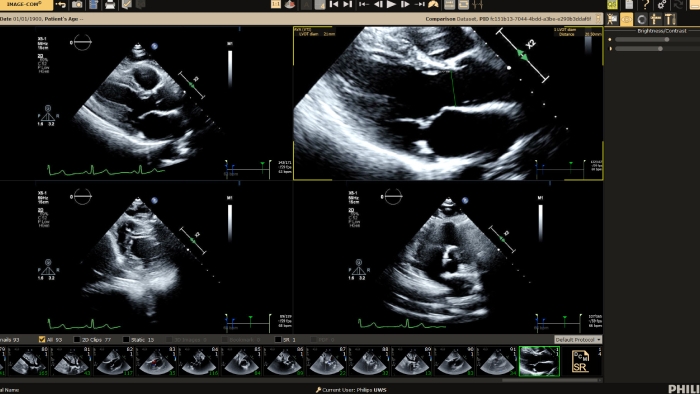

If you were registered for ESC 2023, but were not able to attend the satellite symposium, you can still view it through the ESC website. Top cardiology thought leaders addressed some of the major challenges in peri-interventional and diagnostic echocardiography, such as advancing and complementing imaging techniques during tricuspid valve interventions, a revolutionary imaging workflow for occlusion of the left atrial appendage, and the importance of first-time-right ultrasound imaging during cancer therapy.

• Philips helps deliver diagnostic confidence in echocardiography with Ultrasound Compact 5500CV at ASE 2023

Philips helps deliver diagnostic confidence in echocardiography with Ultrasound Compact 5500CV at ASE 2023